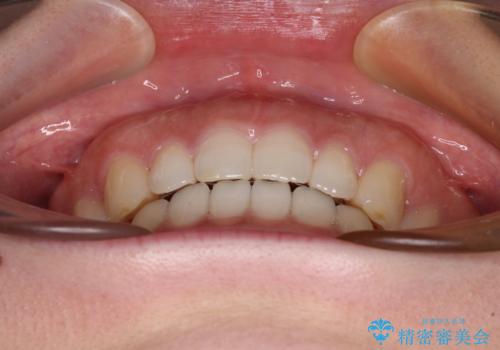

すきっ歯とオープンバイト インビザライン・ライトで改善

オープンバイトのため、奥歯に負担のかかる咬合状態であったので、矯正治療を提案したところ、希望をされました。

すきっ歯程度の軽度の歯列不正であったため、インビザライン・ライトにより咬合改善を行うこととしました。

オープンバイトやすきっ歯は、舌突出癖によりあっという間に後戻りをするため、矯正治療前からトレーニングを行っていただき、更には後戻り防止のワイヤーリテーナーを併用しています。